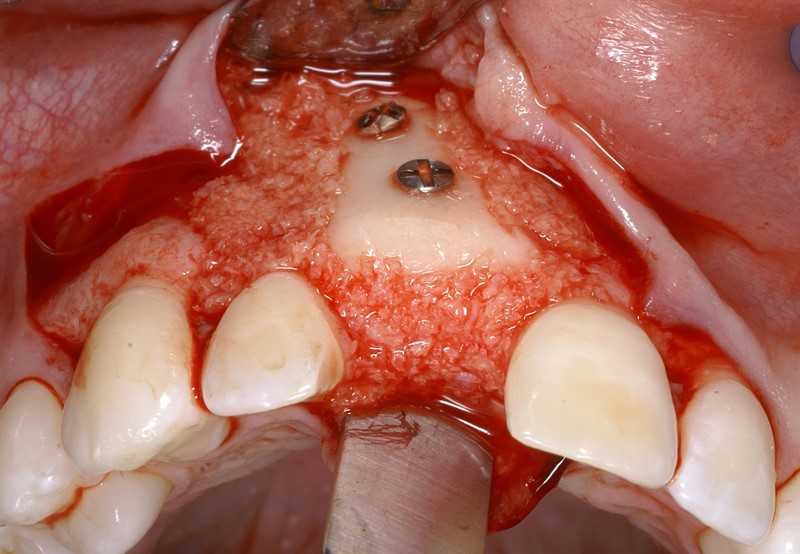

İrəli dərəcədə sümük itkisi mövcud olan, xüsusilə üst çənə ön bölgə və ya alt çənə arxa bölgələrində dental implantların funksional və estetik olaraq uyğun pozisiyada yerləşdirilməsi əksər hallarda ciddi bir problem olaraq qarşımıza çıxır. Problemin həlli əksər hallarda mövcud olan defektin sümükartırma metodları ilə bərpa edilməsi vasitəsilə həyata keçirilir. Bu məqsədlə fərqli metodlar, müxtəlif materialların tətbiqi ilə icra olunur.

Bərpa texnikasının müəyyən edilməsi, sümüyün hansı bölgədə, hansı miqdarda itirilmiş olmasına bağlı olaraq müəyyənləşdirilir. Bərpa üçün tətbiq edilən sümük materialları pasiyentin öz donor bölgələrindən xüsusi metodlarla qazanılmış sümüklər, o cümlədən digər fərdlərdən alınmış və xüsusi qaydada hazırlanmış materiallar, heyvan mənşəli sümükəvəzləyici materiallar və sintetik materiallar olaraq ayrılır.

Bərpa zamanı yerinə görə bu materiallar ya ayrı-ayrılıqda, ya da kombinə olunmuş şəkildə tətbiq oluna bilir. Gündəlik təcrübədə həmçinin pasiyentdən götürülmüş qan nümunələrindən alınmış yüksək bərpaedici xassəyə malik materiallar (PRF) da uğurla tətbiq olunur. Sümükartırma metodlarının tətbiqi sayəsində, çənədə implantların yerləşdirilməsi üçün yetərsiz sümük həcmi olan bölgələrdə sümük miqdarı yetərli duruma gətirilir, uyğun boy və diametrə uyğun implantlar uğurla tətbiq olunur.